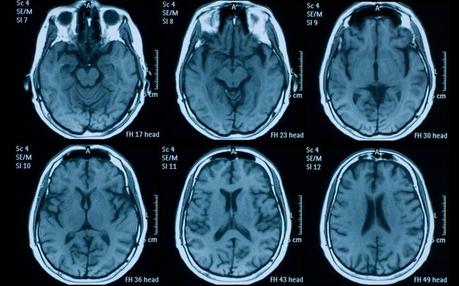

Este avance puede ser especialmente útil para detectar hemorragias muy pequeñas consecuencia de lesiones cerebrales, accidentes cerebrovasculares y aneurismas, según publica la revista 'PNAS'.

La inteligencia artificial sigue avanzando a pequeños pasos para hacerse un hueco en los hospitales. Además de su capacidad para detectar patrones, los equipos médicos pueden utilizarla para maximizar su capacidad de detección de anomalías al analizar distintas pruebas médicas. La última demostración está en un algoritmo desarrollado por científicos de la Universidad de California, que ha conseguido mejores resultados que dos de cada cuatro radiólogos expertos en encontrar pequeñas hemorragias cerebrales en los escáneres. Se trata de un avance que puede ayudar a los médicos a tratar a pacientes con lesiones cerebrales traumáticas, accidentes cerebrovasculares y aneurismas, según publica la revista científica PNAS Además de señalar su ubicación dentro del cerebro, el algoritmo clasifica las anomalías según el subtipo, información que los médicos necesitan para decidir cuál es el mejor tratamiento. Según las pruebas realizadas hasta el momento, el algoritmo proporciona toda esta información con un nivel "aceptable" de falsos positivos y minimizando el tiempo que los médicos necesitarían invertir en revisar los resultados. "Para que esto sea clínicamente útil, el nivel de precisión debe ser casi perfecto. Si una máquina señala muchos falsos positivos, ralentizará al radiólogo y puede provocar más errores", señala Esther Yuh, profesora asociada de radiología en la Universidad de California en San Francisco (UCSF) y coautora del estudio. Una de las claves para conseguir que el algoritmo sea tan preciso son los datos con los que se entrenó al modelo. El estudio utilizó un tipo de aprendizaje profundo conocido como red neuronal convolucional (CNN), que entrena algoritmos con un número relativamente pequeño de imágenes, en este caso 4.396 pruebas de tomografías computerizadas. A pesar del pequeño tamaño de la muestra, el algoritmo consigue tantos aciertos porque las imágenes con las que se le entrenó contenían cantidades ingentes de información: cada pequeña anomalía se delineaba manualmente, píxel por píxel. "La riqueza de estos datos, junto con otros pasos que impidieron que el modelo interpretara el "ruido" como significativo, creó un algoritmo extremadamente preciso", apunta Jitendra Malik, profesora de ingeniería eléctrica y ciencias de la computación en Berkeley. Según recoge Europa Press, los expertos en radiología señalan que la capacidad del algoritmo de encontrar anomalías muy pequeñas y señalar su ubicación en el cerebro es un avance sustancial. "La hemorragia puede ser pequeña y, aun así, ser significativa", precisa Pratik Mukherjee, profesor de radiología en la Universidad de California en San Francisco (UCSF). "Eso es lo que hace que el trabajo de un radiólogo sea tan difícil. Si un paciente tiene un aneurisma, está empezando a sangrar y se le envía a casa, puede morir". La profesora Malik, por su parte, asegura que "dada la gran cantidad de personas que sufren lesiones cerebrales traumáticas todos los días, esto tiene una importancia clínica enorme". Fuente Retina El País